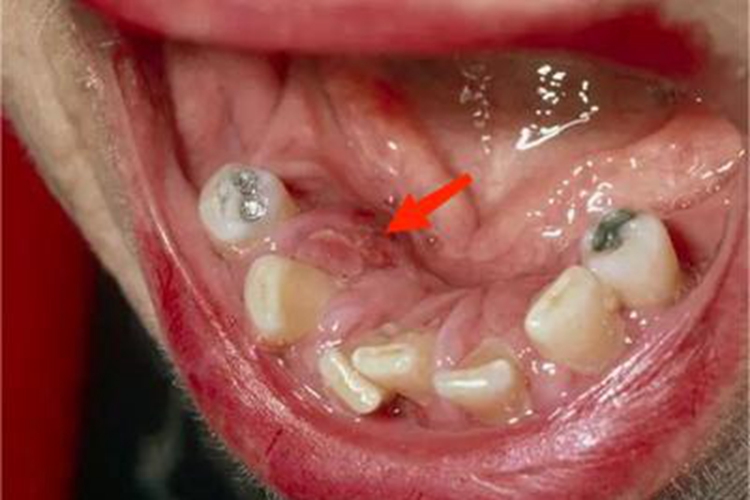

口腔梅毒可导致患处糜烂,暴露出内层基底面,可伴有黏膜充血、弥漫性潮红、渗液等症状,之后表面有灰白色假膜覆盖,患者自觉疼痛。